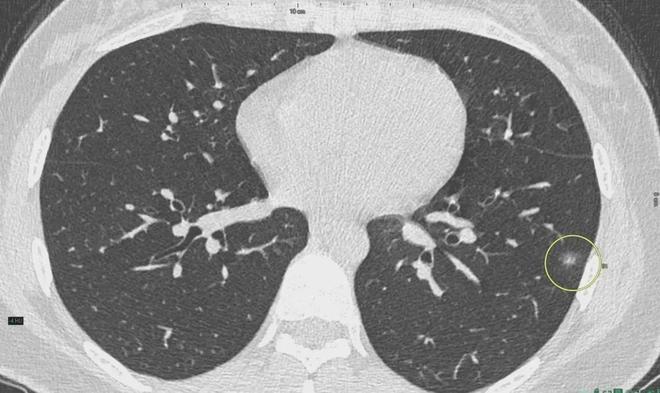

肺結(jié)節(jié)是一種常見的肺部疾病,其發(fā)病率逐年上升,雖然肺結(jié)節(jié)多數(shù)情況下是良性的,但也有可能惡化為肺癌,了解肺結(jié)節(jié)的形成原因?qū)τ陬A(yù)防和治療具有重要意義,本文將為您詳細(xì)解析肺結(jié)節(jié)的形成機(jī)制。